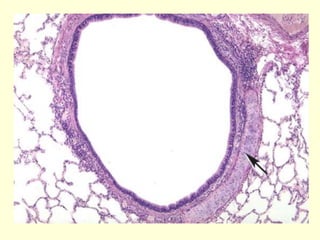

Bronquíolo, propiamente dicho

 Al principio tiene un epitelio seudoestratificado

cilíndrico ciliado que gradualmente se

transforma en un epitelio cilíndrico simple ciliado

conforme el conducto se estrecha.

 La pared del bronquíolo propiamente dicho tiene

muchas capas de músculo liso, el cual se

contrae tras de la preparación histológica y

genera la característica luz estrellada de este

bronquíolo.

 En los bronquíolos no hay glándulas subepite-

liales ni tampoco las placas cartilaginosas.

Bronquíolo terminal

Están revestidos por un epitelio cúbico

simple en el cual hay células de Clara

dispersas entre las células ciliadas.

La capa de músculo liso y el diámetro de

este bronquíolo es menor que en el

propiamente dicho y por lo tanto lo

característico frente al microscopio es ver

una estructura circular bien definida.